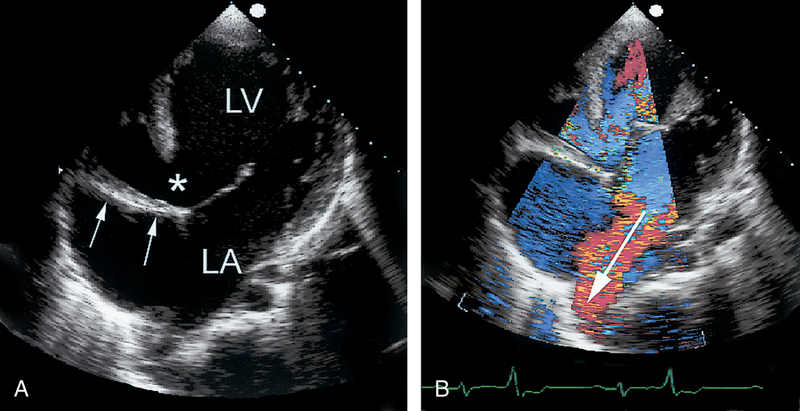

فحوصات تشخيصية لبعض امراض القلب والشرايين التاجية